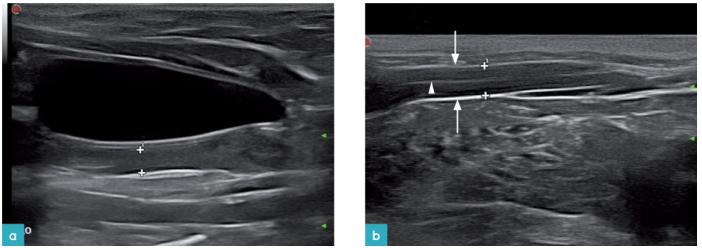

卵巢位于肾脏尾极的外侧,为一圆形或椭圆形的结构,长度小于1cm(图4)。其影像表现与当时所处发情周期有关。使用高频探头可以对无回声的亚毫米级的原始卵泡进行评估(图5),它们通常位于卵巢的外缘(卵巢皮质层含有卵泡,而卵巢髓质内含有血管和神经)。

子宫在超声影像上表现为一管腔样结构,子宫体位于膀胱和结肠之间,子宫角位于后腹部的背外侧。近期研究表明,由于母猫的子宫颈缺乏局:部增厚,子宫体缺乏靶样外观,所以不如其他物种容易看到子宫。可见子宫矢状面上外围有一明显的高回声光晕(浆膜层),矢状面上的光晕会比横截面上更加明显。有些母猫的子宫在超声影像上可以区分出两层结构。正常的子宫腔内是不含有任何液体的,但能在子宫内看到一条:高回声亮线,该高回声亮线为子宫内膜的回声(图6)。